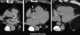

Coronary artery disease - hyperlipidemia - hypertension - diabetes - osteoporosis

Statins, also known as HMG-CoA reductase inhibitors, are a class of lipid-lowering medications that reduce illness and mortality in those who are at high risk of cardiovascular disease. They are the most common cholesterol-lowering drugs.Low-density lipoprotein (LDL) carriers of cholesterol play a key role in the development of atherosclerosis and coronary heart disease via the mechanisms described by the lipid hypothesis. [Source: Wikipedia ]